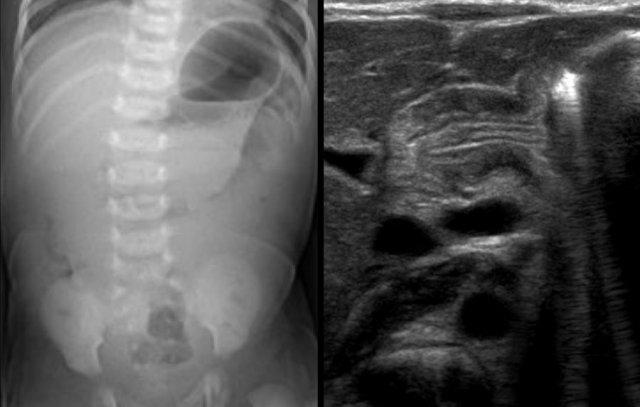

Các hình ảnh cho thấy một trường hợp điển hình của viêm ruột hoại tử với khí trong thành ruột.

Trên hình chụp tia ngang, không có dấu hiệu khí tự do trong ổ bụng.

Đây là hình ảnh của một trẻ sơ sinh phát triển viêm ruột hoại tử.

Ở giai đoạn sớm này, X-quang chỉ cho thấy hình ảnh giãn ruột không đặc hiệu.

Ở giai đoạn này, không thể xác lập chẩn đoán.

Hình ảnh bên trái được chụp 6 ngày sau sinh, cho thấy ruột giãn với khí trong thành ruột.

Hình chụp thụt tháo đại tràng lúc 6 tuần tuổi cho thấy hẹp ở đại tràng xuống (mũi tên).